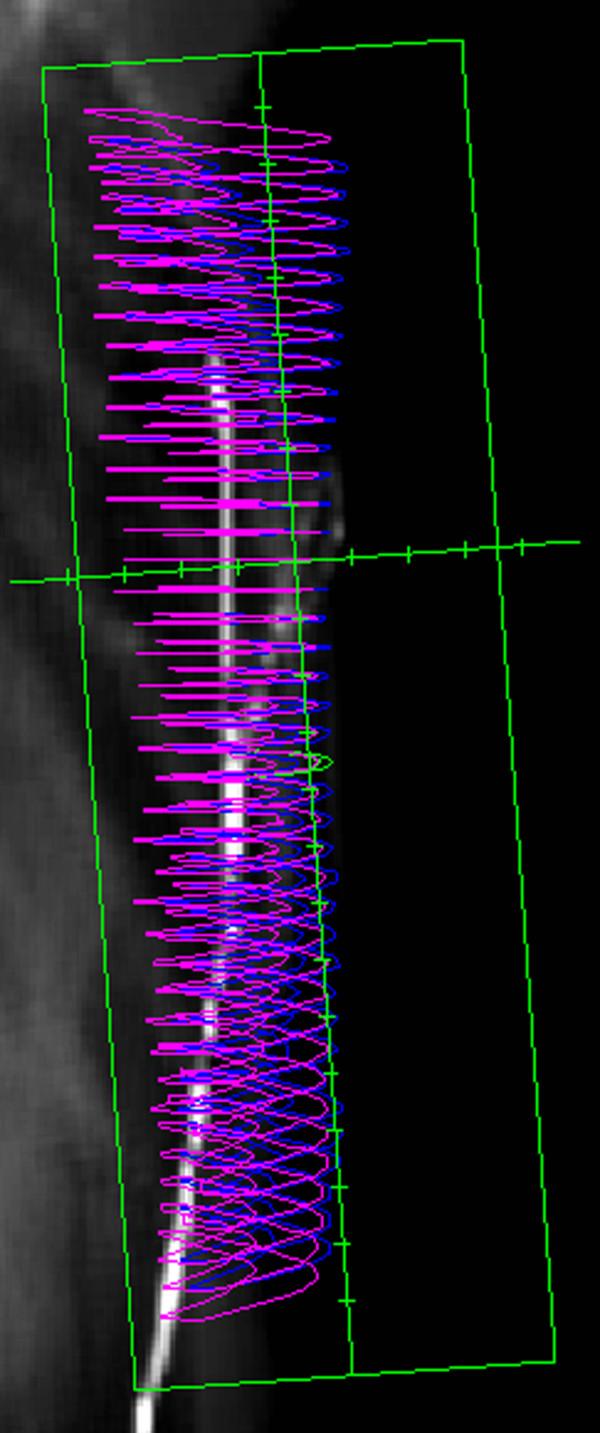

CT-Simulation scans of 22 post-mastectomy patients were used. Chest wall for clinical target volume (CTV) and a volume including 2-mm surface thickness of the chest wall for skin structures were delineated. Precise PLAN 2.11 treatment planning system (TPS) was used for 3D-CRT planning. 50 Gy in 25 fractions were prescribed using tangential fields and 6-MV photons. Six different frequencies of bolus applications (0, 5, 10, 15, 20, and 25) were administered. Cumulative dose-volume histograms were generated for each bolus regimen. The minimum, maximum and mean skin doses associated with the bolus regimens were compared. To test the accuracy of TPS dose calculations, experimental measurements were performed using EBT gafchromic films.

The mean, minimum and maximum skin doses were significantly increased with increasing days of bolus applications (p < 0.001). The minimum skin doses for 0, 5, 10, 15, 20, and 25 days of bolus applications were 73.0% +/- 2.0%, 78.2% +/- 2.0%, 83.3% +/- 1.7%, 88.3% +/- 1.6%, 92.2% +/- 1.7%, and 93.8% +/- 1.8%, respectively. The minimum skin dose increments between 20 and 25 (1.6% +/- 1.0%), and 15 and 20 (4.0% +/- 1.0%) days of bolus applications were significantly lower than the dose increments between 0 and 5 (5.2% +/- 0.6%), 5 and 10 (5.1% +/- 0.8%), and 10 and 15 (4.9% +/- 0.8%) days of bolus applications (p < 0.001). The maximum skin doses for 0, 5, 10, 15, 20, and 25 days of bolus applications were 110.1% +/- 1.1%, 110.3% +/- 1.1%, 110.5% +/- 1.2%, 110.8% +/- 1.3%, 111.2% +/- 1.5%, and 112.2% +/- 1.7%, respectively. The maximum skin dose increments between 20 and 25 (1.0% +/- 0.6%), and 15 and 20 (0.4% +/- 0.3%) days of bolus applications were significantly higher than the dose increments between 0 and 5 (0.2% +/- 0.2%), 5 and 10 (0.2% +/- 0.2%), and 10 and 15 (0.2% +/- 0.2%) days of bolus applications (p < or = 0.003). The TPS overestimated the near-surface dose 10.8% at 2-mm below the skin surface.